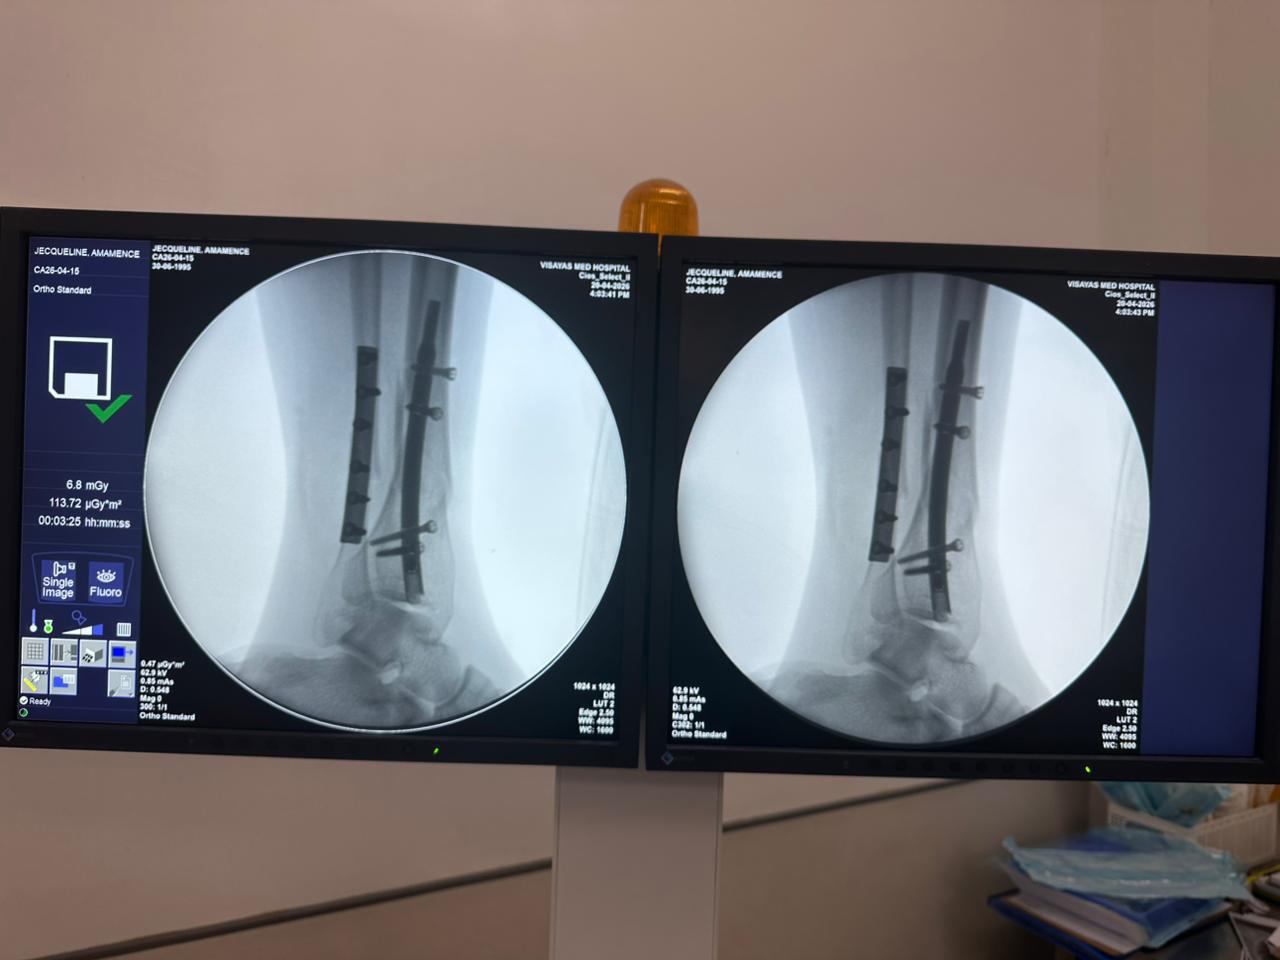

Estudio de caso de fijación de clavo tibial distal con soporte de placa para peroné

Imágenes:

Radioscopia intraoperatoria con arco en C, vistas AP y lateral

Este caso involucró la fijación de la tibia distal utilizando un clavo tibial distal intramedular. La fluoroscopia intraoperatoria confirmó la posición del clavo, los tornillos de bloqueo distales y la fijación de la placa del peroné.

clavo-tibial-distal-fluoroscopia-intraoperatoria-CZMEDITECH (4)

clavo-tibial-distal-fluoroscopia-intraoperatoria-CZMEDITECH